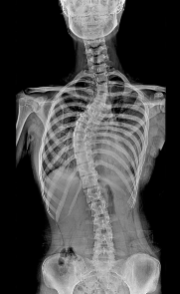

척추 측만증 증상 원인 치료방법 등 척추 측만증과 관련된 정보를 알아보도록 하겠습니다. 척추측만증은 척추의 관절 연골과 뼈가 마모되어 생기는 질환으로, 허리와 목 부위에서 가장 흔하게 발생합니다. 나이가 들면서 발생하는 질환으로, 디스크의 압력이 증가되거나 관절연골에 마모가 발생해 척추의 안정성이 떨어지게 됩니다. 이로 인해 허리나 목이 뻐근하고 아프게 느껴지며, 심한 경우는 근육 약화와 마비 등의 증상을 보일 수 있습니다. 척추측만증은 노화에 따라 발생하는 질환으로, 운동이나 근력강화 운동 등을 통해 예방할 수 있습니다.

척추측만증은 척추의 관절 연골과 뼈가 마모되어 생기는 질환으로, 다음과 같은 증상을 보입니다.